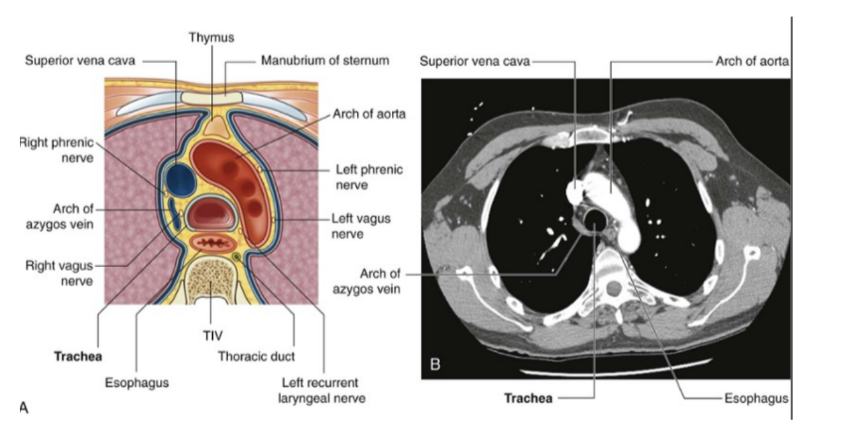

Mesiastinum

The central portion of the thoracic cavity that separates the pleural cavities

Extends from the sternum to the bodies o the vertebrae, and from the superior thoracic aperture to the diaphragm

Contains many structures — such as

Thymus, pericardial sac (& thus heart), trachea, and many major arteries & veins —

Also serves as a place of passage for many different structures

Subdivisions of the mediastinum

Divided into 2 smaller sections at the transverse plane, extending from the sternal angle to the intervertebral disc betwen TIV & TV

Splits into —

Superior mediastinum

Inferior mediastinum

Further partitioned into the anterior, middle, and posterior mediastinum by the pericardial sac

Superior mediastinum

Extends inferiorly from the superior thoracic aperture to the horizontal plane including sternal angle anteriorly & passes approximately through the IV disk of T$ & T% vertebrae posteriorly — often referred to as the transverse thoracic plane

Found posterior to the manubrium of the sternum & anterior to the bodies of the first 4 thoracic vertebraes

In continuation with the neck above & inferior mediastinum below

Major recognizable structures —

Trachea & esophagus

Trachea —

Midline structure palpable in the jugular notch as it enters the superior mediastinum

Divides into right & left main bronchi just inferior to the transverse plane between sternal angle & vertebral level TIV/V — also where the esophagus continues into the posterior mediastinum

Esophagus —

Posterior to the trachea & immediately anterior to the vertebral column

Nerves of the superior mediastinum

At the level of the superior mediastinum we mainly have the vagus & diaphragmatic/phrenic nerve —

Right & left vagus nerves of superior mediastinum

Right vagus nerve —

Enters superior mediastinum between right brachiocephalic vein & brachiocephalic trunk

Then goes down along trachea & passes posterior to roof of right lung then near esophagus to arrive at diaphragm

Left vagus nerve —

Enters mediastinum between left brachiocephalic vein & left common carotid artery

Passes posteriorly to the root of the left lung

At the level in which it crosses to the lateral side of the arch of the aorta there is the origin of the laryngeal nerve